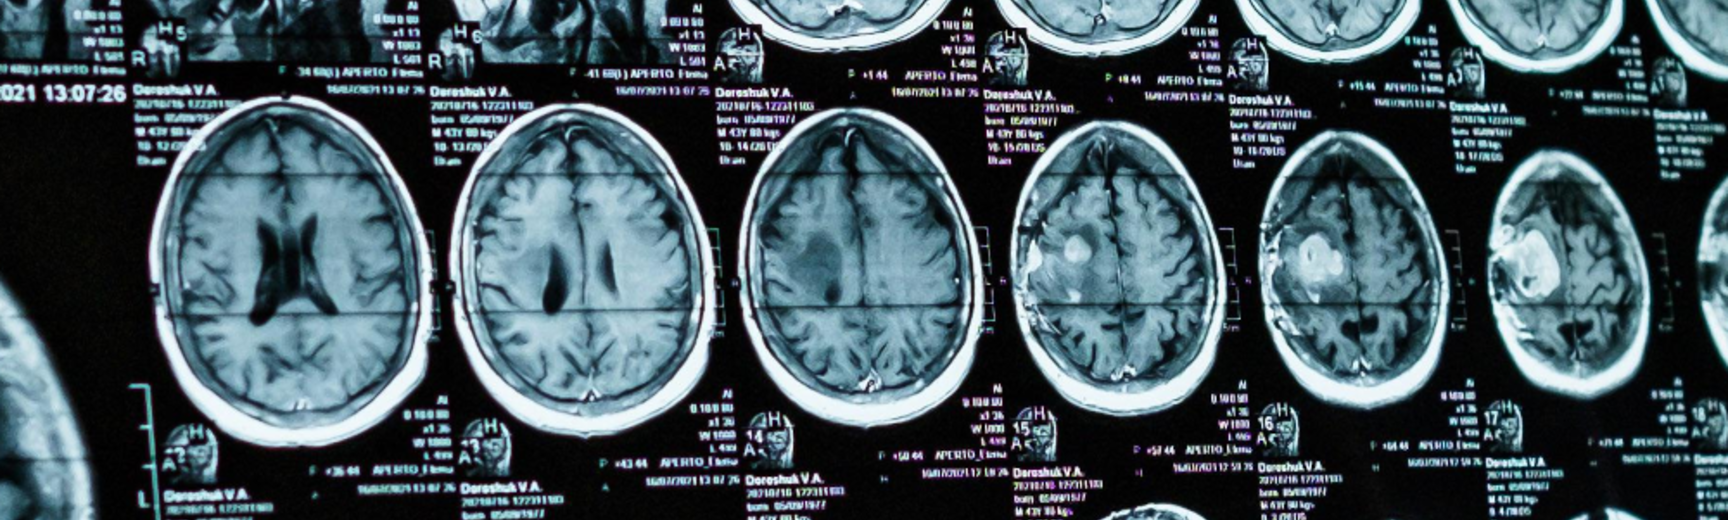

Kahane, G., Skene, L., Wilkinson, D. and Savulescu, J. (2009) 'Neuroimaging and the Withdrawal of Life-Sustaining Treatment from Patients in the Vegetative State', Medical Law Review, Vol: 17(2) [open access]

Levy, N., (2009), 'What Difference does Consciousness Make?' Monash Bioethics Review, Vol: 28 (2) [open access]Wilkinson, D., Kahane, G., Horne, M. and Savulescu, J. (2009), 'Functional neuroimaging and withdrawal of life-sustaining treatment from vegetative patients', Journal of Medical Ethics, Vol: 35 pp. 508-511 [open access]